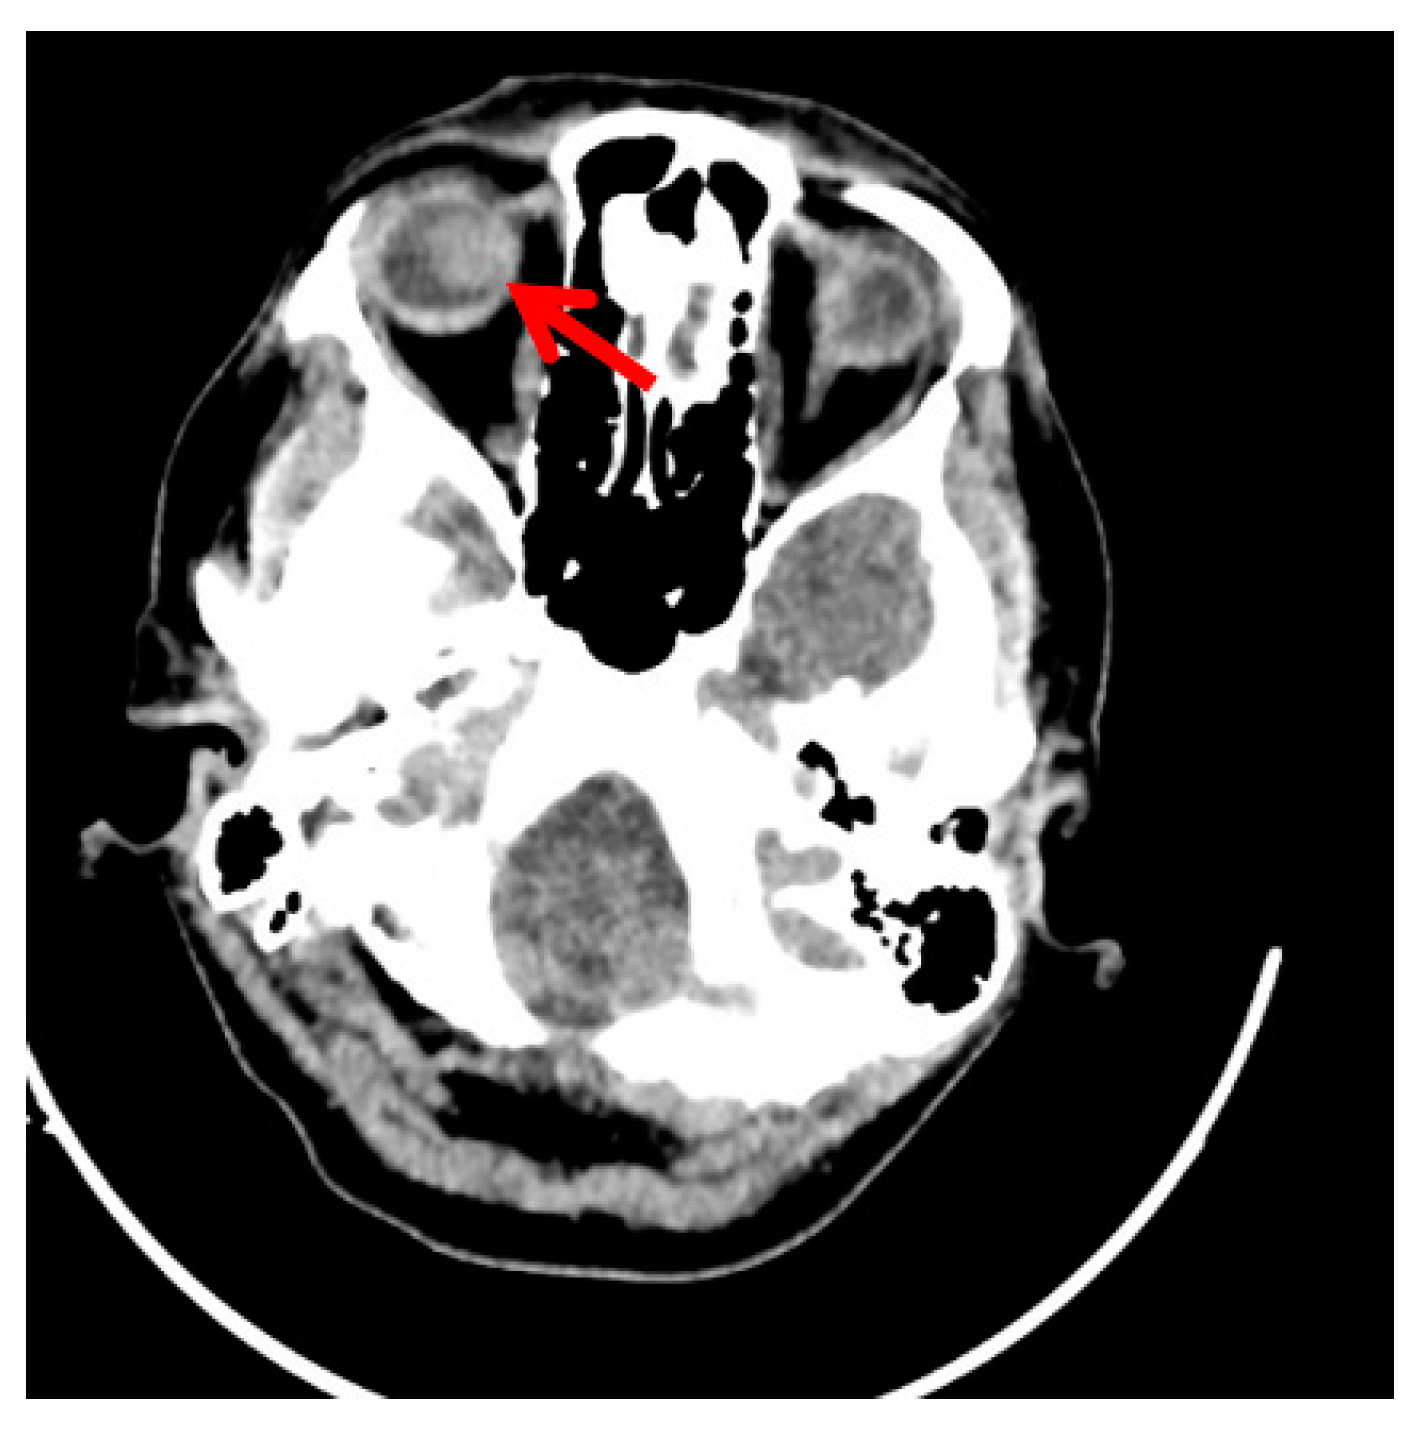

Clinical Scenario

- Vaidya, P.; Mehta, A.; Ragab, O.; Lin, S.; In, G.K. Concurrent radiation therapy with programmed cell death protein 1 inhibition leads to a complete response in advanced cutaneous squamous cell carcinoma. JAAD Case Rep. 2019, 5, 763–766. [Google Scholar] [CrossRef]